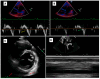

Background. Pericarditis has a heterogeneous clinical spectrum and rate of relapse. Data on aetiology, real-life treatment strategies, and long-term course from contemporary pericarditis cohorts are lacking. Methods. Pericarditis patients referred to the Cardioimmunology Outpatient Clinic at Padua University Hospital in 2001-2020 were retrospectively included. Kaplan-Meier method was used for recurrence-free survival probability estimation. The appropriateness of treatment was assessed based on the European Society of Cardiology guidelines. Results. One-hundred forty-four patients (57% males, mean age 50 years) followed up for 18 months (IQR 7-45) were included; of those, 52% had acute, 35% recurrent, 8% incessant, and 5% chronic pericarditis; 9% had cardiac tamponade at diagnosis. Time to pericardial effusion resolution was 53 days (IQR 16-124); median medical treatment duration was 87 days (IQR 48-148). Treatment was readjusted following the ESC guidelines for nonsteroidal anti-inflammatory drugs in 29% of the cases, steroids in 12%, and colchicine in 25%. Eleven (8%) patients were treated with anti-IL1 agents. Recurrence-free survival probability was 86% at 1st-year follow-up, and 23 patients (16%) had at least one recurrence, with a mean of two relapses per patient. Compared to patients without recurrences, they had a higher frequency of cardiac tamponade (27% vs. 6%, p = 0.006) and left bundle branch block (14% vs. 1%, p = 0.034). Out of the 144 patients, 5 (3%) were diagnosed as having constrictive pericarditis at first evaluation at our clinic, underwent successful pericardiectomy, and are currently alive and asymptomatic. Conclusions. When treated following a guideline-based approach, pericarditis has a favourable evolution. A relevant quote of cases benefits from the treatment readjustment of previously prescribed medical therapy when not in line with ESC recommendations. Cases relapsing despite treatment readjustment should receive anti-IL1 therapies.